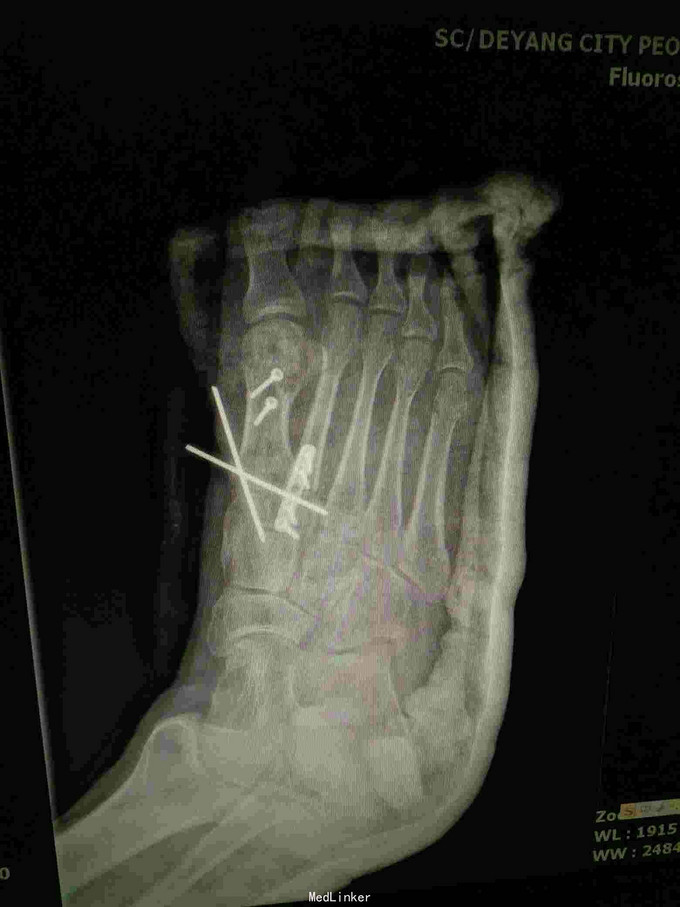

查体:右足畸形肿胀,足背少许擦挫伤,无开放性伤口,明显压痛,右足远远端感觉及血运可。 x片:右足第1、2跖骨基底部骨折,第3跖骨基底部可疑骨折; ct:右足第1~4跖骨骨折。

诊断:右足第1、2跖骨粉碎性骨折;右足lisfrance损伤; 治疗:石膏固定,消肿止痛,行右足跖骨骨折切开复位内固定,第1跖骨钢钉及克氏针固定,第2跖骨钢板固定。